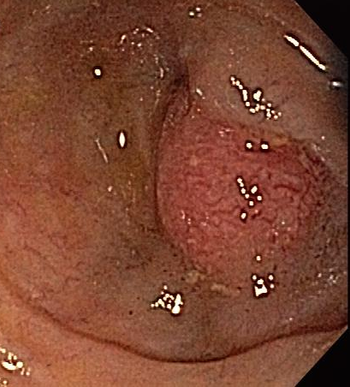

Test your knowledge of this GI finding with questions on diagnosis, laboratory screening, and removal.

For carcinoid tumors of the GI tract, the rate of metastasis is related to size. Small tumors may be resected endoscopically but lesions 1 cm or larger require surgical resection.